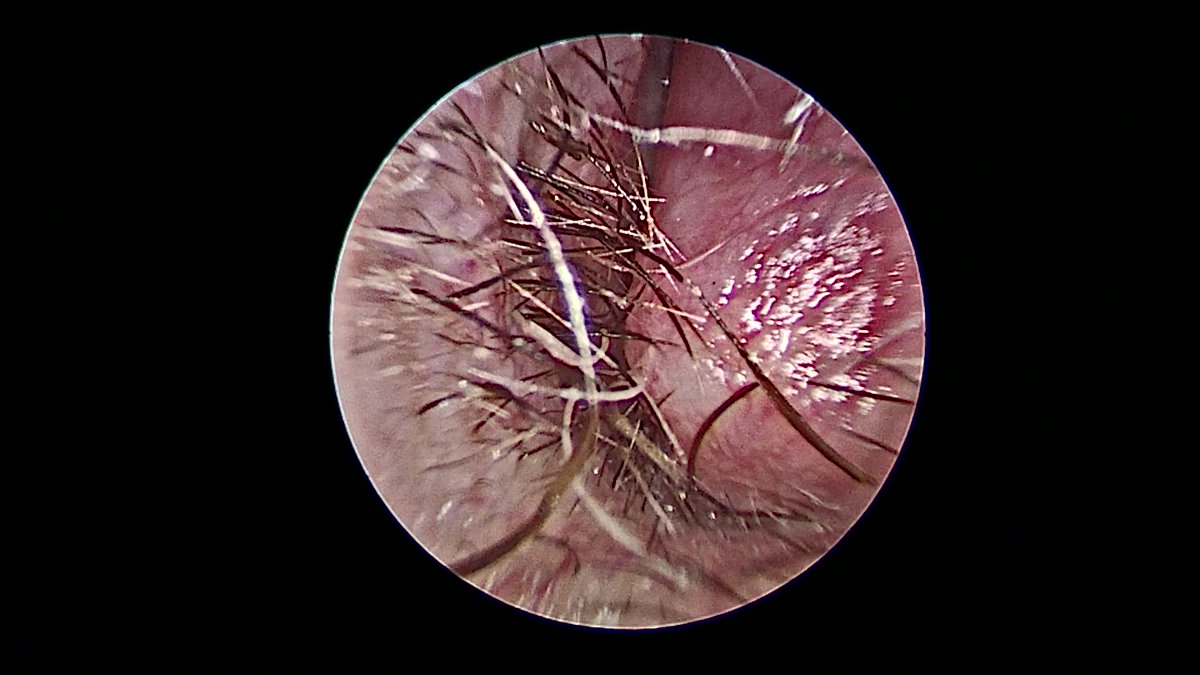

@ent_ams @JohnCraigNose @henryfordent What's under the microscope?

@JohnCraigNose @TroyWoodardMD @henryford Great case! A few questions from a trainee: When do you place packing (higher flow leak? Larger defect? )Can you link to the adhesive used? What kind of eye effects do you see (or not) with taking the vidian?